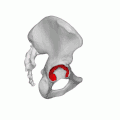

Суставные полулунные поверхности вертлужных впадин тазовых костей участвующие в образовании тазобедренных суставов (левого и правого) отмечены красным